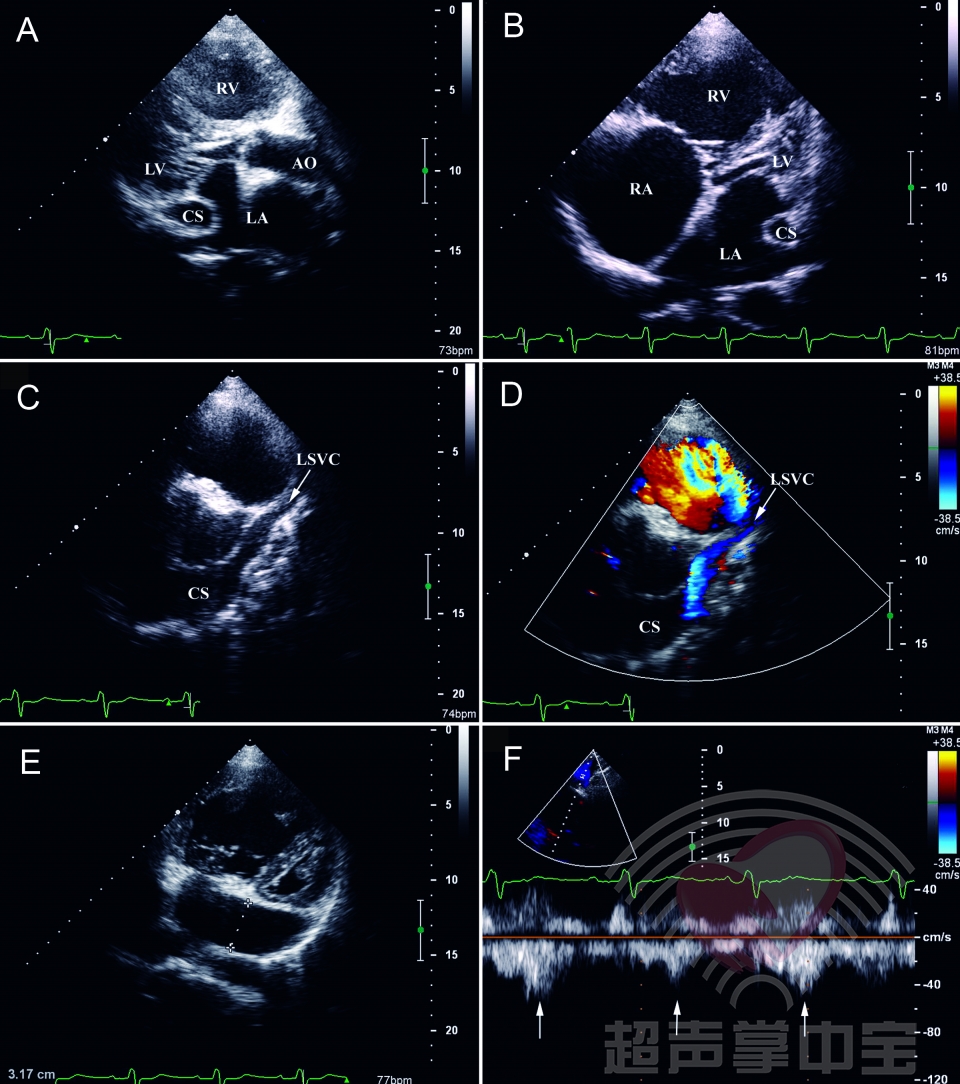

永存左上腔静脉图谱

永存左上腔静脉图谱,

永存左上腔静脉

永存左上腔静脉分型

永存左上腔静脉示意图